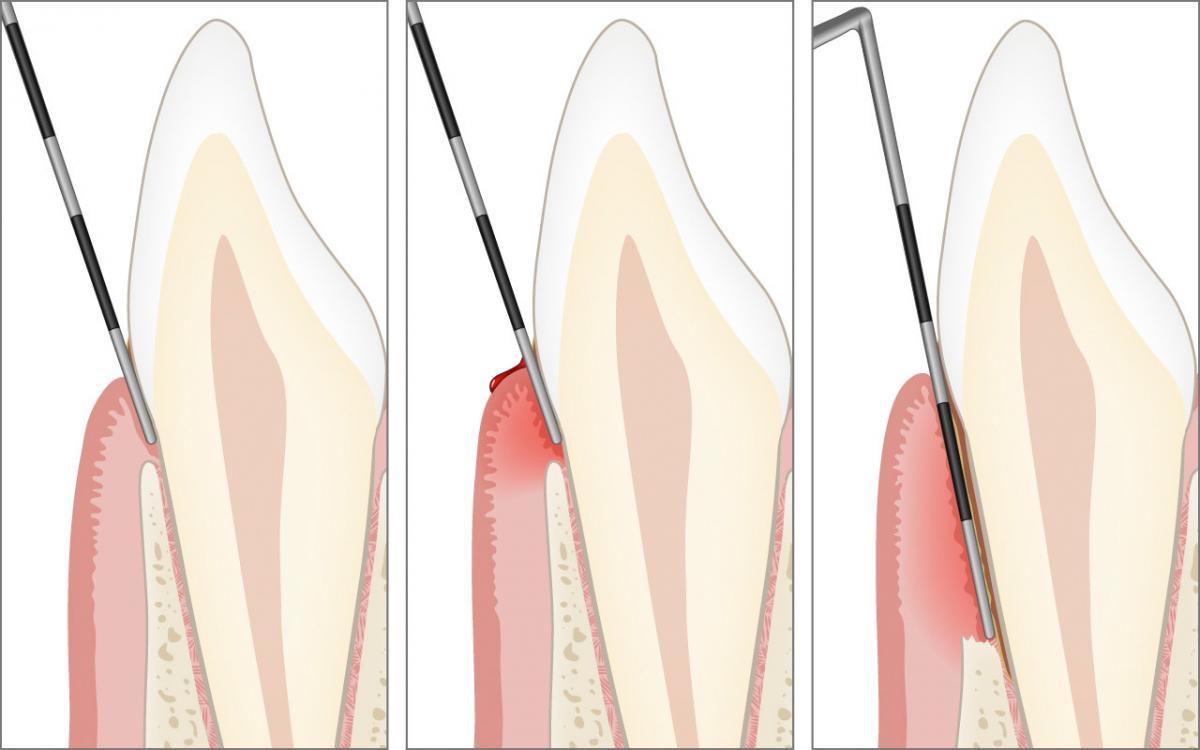

Erst die korrekte klinische Untersuchung in der Zahnarztpraxis mit einer sogenannten Zahnfleischsonde (Parodontalsonde) kann Aufschluss geben, ob das Zahnfleisch gesund ist, eine Zahnfleischentzündung (Gingivitis) oder bereits eine Erkrankung der Zahnverankerung (Parodontitis) vorliegt.

Mit einer Zahnfleischsonde (Parodontalsonde) wird an ausgewählten Stellen schonungsvoll und millimetergenau die Eindringtiefe am Zahnfleischrand gemessen.

Die millimetergenaue klinische Sondierung mit der Zahnfleischsonde zur Ausmessung der Zahnfleischtaschen und der Höhe des Kieferknochens sind zur Diagnose der Parodontitis unverzichtbar.